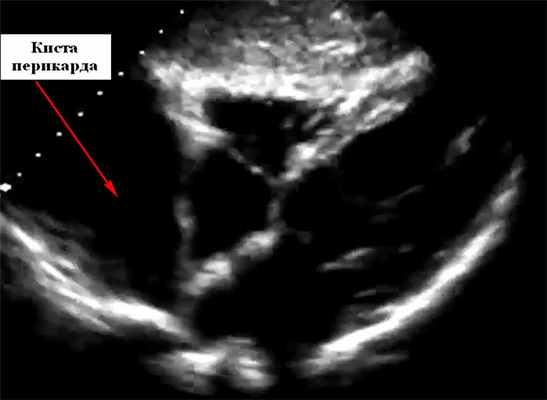

Характерная находка на рентгенограмме грудной клетки - округлая, четко очерченная рентгеноконтрастное образование под правым кардио-диафрагмальным углом, прилегающая к диафрагме. Сообщалось о других местах, таких как левый сердечно-диафрагмальный угол или где-либо еще в верхнем средостении. На эхокардиографии они выглядят как локализованное свободное от эхонегативное пространство, прилегающее к границе сердца, чаще всего около правого предсердия. Они могут исказить нормальную форму предсердия. При эхокардиографии киста выявляется как округлая эхонегативная кистозная структура, прилегающая к правому предсердию или желудочку, которая не сообщается с перикардиальным пространством. Чреспищеводная эхокардиография может дать лучшее определение ее размерам. Большие кисты перикарда могут привести к сдавлению правой камеры сердца и появлению симптомов. Цветное допплеровское картирование и импульсный допплеровский спектр при настройках на низкой скорости можно использовать, чтобы гарантировать отсутствие фазового потока внутри образования.

На УЗИ кисты перикарда необходимо дифференцировать от локализованного выпота в перикарде, увеличения камеры сердца, диафрагмальной грыжи и злокачественных опухолей. Двумерная эхокардиография может легко отличить анэхогенное содержимое перикардиальной кисты от солидных структур. Типичное расположение кист перикарда в правом сердечно-диафрагмальном угле является еще одним ключом к разгадке, хотя они также могут быть обнаружены в левом сердечно-диафрагмальном углу, воротах и верхнем средостении.

Магнитно-резонансная томография сердца (КМРТ) или компьютерная томография (КТ) обычно используются для подтверждения диагноза, выяснения других анатомических деталей и отличия от новообразований и аневризм. На картинке ниже представлена гигантская киста перикарда на эхокардиографии.

В марте 2012 г. выполнена селективная ангиография коронарных артерий, по результатам которой гемодинамически значимых сужений коронарных артерий выявлено не было. По результатам иммунологического исследования данных, свидетельствующих о миокардите, не получено. По данным эхокардиографии выявлена инкапсулированная полость (киста перикарда?), деформирующая правое предсердие, правый желудочек, размерами 3,5×6 см. Левый желудочек: толщина межжелудочковой перегородки (диаст.) – 1,1 см, толщина задней стенки левого желудочка (диаст.) – 0,8 см, конечный систолический размер – 3,5 см, конечный диастолический размер – 5,3 см, конечный диастолический объем – 133 мл, конечный систолический объем – 51 мл, ударный объем – 82 мл, фракция выброса (по Тейхольцу) – 62%. Левое предсердие: диаметр – 3,5 см. Митральный клапан: не изменен, движение створок разнонаправленное, диаметр фиброзного кольца – 2,7 см. Аортальный клапан: не изменен, диметр фиброзного кольца – 2,4 см. Аорта: диаметр на уровне синуса Вальсальвы – 3,7 см; диаметр восходящего отдела – 3,8 см. Трикуспидальный клапан: не изменен, диаметр фиброзного кольца – 3,5 см.